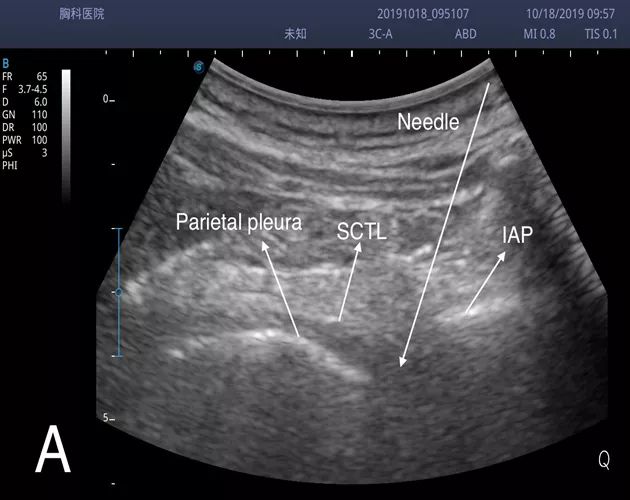

b.重点介绍“IAP外向平面内入路”。其超声影像及相关解剖如下[2]:

(TPV space:胸椎旁间隙,IAP:下关节突,iimb:肋间内膜,SCTL:上位肋横突韧带,p:壁层胸膜,es:竖脊肌,trap:斜方肌,lc/eim:肋提肌/肋间外肌,ST:交感干。Anesthesiology 2015; 123:459-74)

(右上图示操作时探头的放置和进针方向,非该患者本人)

(A、B分别为注药前后椎旁间隙影像。图B见胸膜下移,所示液性暗区为局麻药液。)